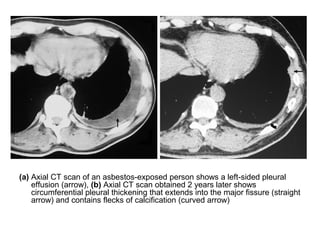

(a) Axial CT scan of an asbestos-exposed person shows a left-sided pleural

effusion (arrow), (b) Axial CT scan obtained 2 years later shows

circumferential pleural thickening that extends into the major fissure (straight

arrow) and contains flecks of calcification (curved arrow)